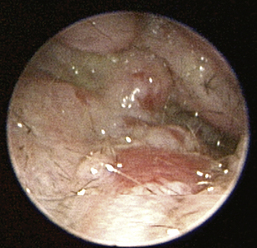

image

Figure 20-12 Scaly pars tensa in a dog with otitis media.

(Courtesy of Dr. Lynette Cole, The Ohio State University, Columbus, Ohio.)